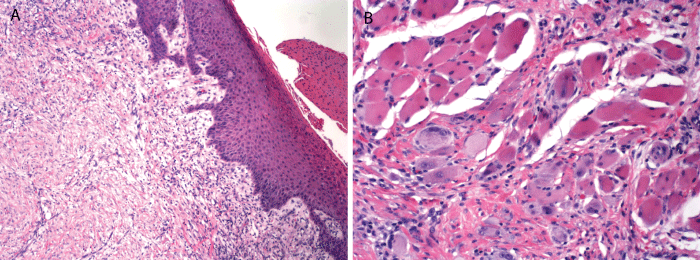

The surgical excision specimen from the reconstructive surgery revealed mild keratosis of the epithelium, submucosal fibrosis and skeletal muscle atrophy consistent with a scarred infarct (Figure 5A and Figure 5B). The patient healed uneventfully and post-op photos were taken at two weeks. The final result from the surgery restored both function and enhanced esthetics to the lower lip (Figure 6).

Figure 5: Photomicrograph of surgical biopsy specimen at time of reconstructive surgery. Mild keratosis, fibrosis and atrophy of skeletal muscle consistent with a healed infarct (A) (magnification X 200); Muscle atrophy with clumping of nuclei to form multinucleated skeletal muscle fibers (B) (magnification X 400).